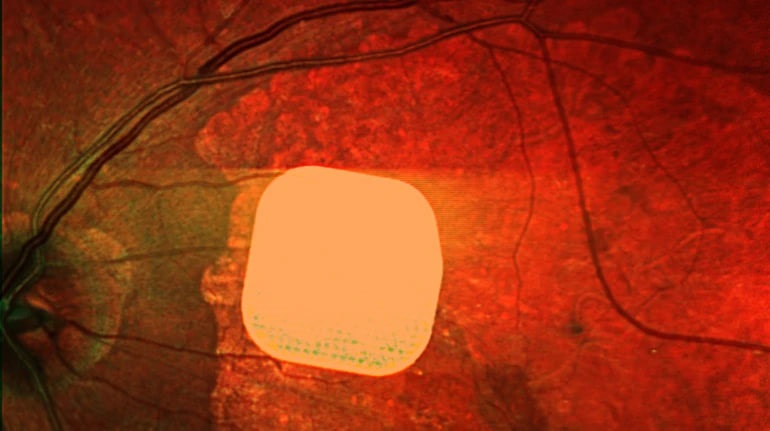

Британські лікарі з лондонської клініки Moorfields Eye Hospital спільно з колегами з інших європейських медичних закладів випробували новий електронний імплант Prima, який може допомогти відновити частково зір у пацієнтів із макулодистрофією. Цей мікрочип встановлюють під сітківку ока пацієнта і підключають до системи окулярів доповненої реальності. Під час дослідження, в якому взяли участь 38 пацієнтів, 84% з них після адаптації змогли розрізняти літери, цифри та слова. Лікарі вважають, що ця технологія може значно поліпшити якість життя людей із важкими зоровими проблемами, дозволяючи їм читати та бути більш незалежними.